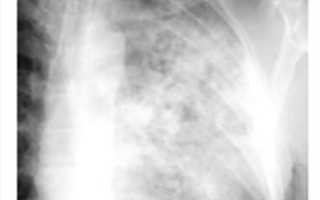

Во II стадии на фоне мелкоячеистого рисунка видны множественные мелкие узелковые тенеобразования, разбросанные довольно равномерно в обоих легочных полях на всём их протяжении, но больше в средне-нижних отделах. Контуры их чёткие. Элементы легочного рисунка как бы исчезают. Расширенные тени корней лёгких представляются как бы обрубленными от своих ветвей (симптом «обрубленного корня»), в дальнейшем могут подвергнуться сморщиванию. При переходе процесса во П стадию больной начинает ощущать выраженную одышку, больше выражен кашель, иногда боли в груди. Одышка медленно постепенно нарастает, развивается дыхательная недостаточность I-II степени.

В III стадии силикоза происходит слияние узелков, усиленное развитие соединительной ткани. При этом на рентгенограмме определяется наличие крупных фокусных образований, наряду с выра- женным фиброзом лёгких. В лимфатических узлах корня иногда можно обнаружить обыз- вествление по их наружному краю (симптом «яичной скорлупы»). В III стадии, когда фиброз и эмфизема увеличивается, развивается легочно- сердечная недостаточность.

II стадия силикоза, а особенно III — очень часто осложняется туберкулёзом — силикотуберкулёз. При силикозе чаще всего развивается очаговая, реже другие формы туберкулеза легких. Помимо этого, встречаются силикотуберкулезный бронхоаденит, узловой и так называемый массивный силикотуберкулез.

В отличие от туберкулёза, очаги при силикозе локализуются в латеральных частях средних отделов легочных полей, верхушечные области либо вовсе свободны, либо очаги находятся в них в небольшом числе. Очаговые тени при силикозе более интенсивны чем при диссеминированном туберкулёзе, контуры их более чётки

В то же время, в отличие от туберкулёза, во II-Ш стадии неосложнённого силикоза симптомы интоксикации не выявляются. Если к одышке, выраженному кашлю присоединяются симптомы интоксикации: повышение температуры, озноб, поты, похудание, повышение СОЭ, умеренный лейкоцитоз, лимфопения, уменьшение уровня альбуминов и нарастание глобулинов, то можно думать о развитии силикотуберкулёза. При этом рентгенологическое исследование позволяет выявить, наряду с силикозом, изменения, характерные для туберкулёза: наличие туберкулёзных очагов, инфильтратов, полостей распада. У большинства больных в мокроте обнаруживают БК.

Для диссеминированного туберкулеза, образующегося на фоне силикоза, характерна довольно типичная рентгенологическая картина.

В этих случаях туберкулезные очаги более полиморфны. Они располагаются преимущественно в верхних отделах легких, а под влиянием туберкулостатической терапии подвергаются более или менее выраженной инволюции. При хроническом диссеминированном туберкулезе очаги, как правило, различной плотности, определяются плевральные изменения, иногда отмечаются признаки цирроза легких. Недавно возникшие эластичные каверны на фоне узелкового силикоза имеют чаще неправильную округлую форму и выявляются более четко только на томограмме. Фиброзно-кавернозный туберкулез характеризуется наличием оформленных каверн с выраженными, фиброзными стенками. Однако следует иметь в виду возможность развития силикотических каверн, которые возникают в толще силикотических узлов. Они имеют неправильную щелевидную форму с неровными внутренними ландкартообразными очертаниями. Как правило, в них не виден уровень жидкости. В большинстве случаев формирование таких каверн связано с влиянием туберкулезной инфекции. Клинически при фиброзно-кавернозном туберкулезе отмечаются симптомы интоксикации, физические изменения в легких, часто имеет место бацилловыделение. Заживление каверн наблюдается редко даже при рациональной антибактериальной терапии. При этом на месте отдельных полостей могут образоваться силикотуберкуломы.

- Рентгенография легких. При силикотуберкулезе может отражать различную картину: на фоне диффузного крупно-сетчатого фиброза и типичных для силикоза симметричных узелковых высыпаний в средних и нижних долях появляются туберкулезные очаги, инфильтраты, силикотуберкуломы, каверны, преимущественно расположенные в верхушечных областях.